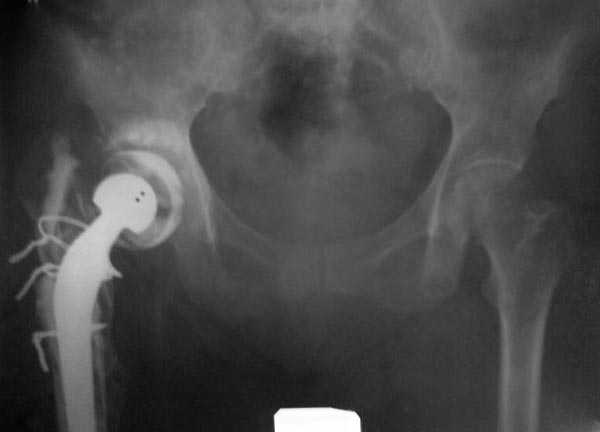

Из предложенных вариантов быстрейший результат можно ожидать после поэтапного эндопротезирования.

"Антибиотико-цементные" спейсеры после купирования

инфекции уже после первого этапа позволяют больным

передвигаться самостоятельно, иногда нагружая конечность годами.

Как-то показывал случай после осложненного тотального эндопротеза, сперва из-за отсутствия экономических возможности, а затем привыкшая к своей участи вот уже более 8 лет ходит на временном "протезе-спейсере".

Полость вертлужной впадины и проксимальное бедро были заполнены custom made временным протезом из цемента.

В вертлужную полость устанавливается цемент и головкой протеза выдавливается выемка, т.е. создается место для головки. В проксимальное бедро устанавливается заранее подготовленный цементный бедренный компонент.

Через пару месяцев после улучшения мягкотканой

кондиции можно приступить к окончательному протезу.